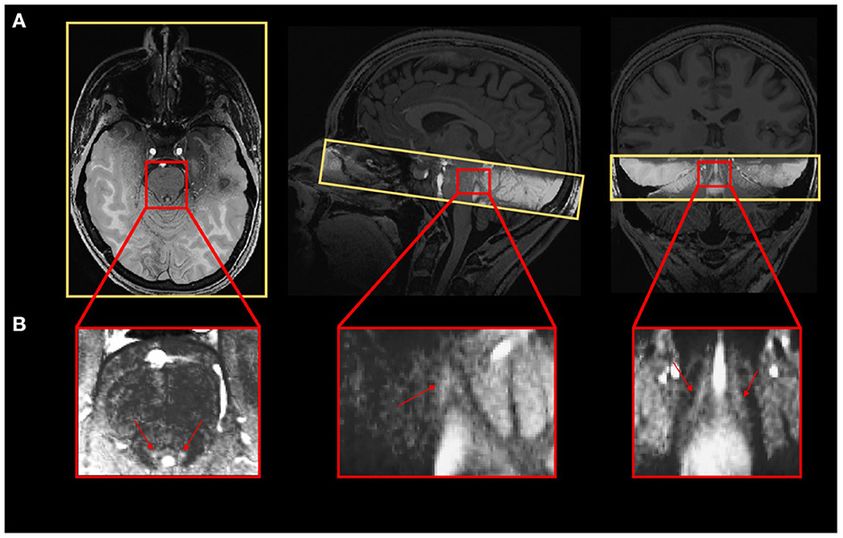

➡ Le locus coeruleus (LC) du tronc cérébral influence un large éventail de processus cérébraux, y compris la cognition.

➡ Le contraste du LC est un marqueur reconnu de l'intégrité du LC qui consiste en une hyperintensité locale sur des images structurelles spécifiques d'imagerie par résonance magnétique (IRM).

➡ La petite taille du LC a toutefois rendu difficile sa caractérisation fonctionnelle chez l'homme, y compris chez les personnes âgées.

➡ Ici, les scientifiques ont voulu déterminer si l'activation du LC dans une tâche de négativité de discordance changeait avec le vieillissement et si la réponse fonctionnelle du LC était associée au contraste du LC.